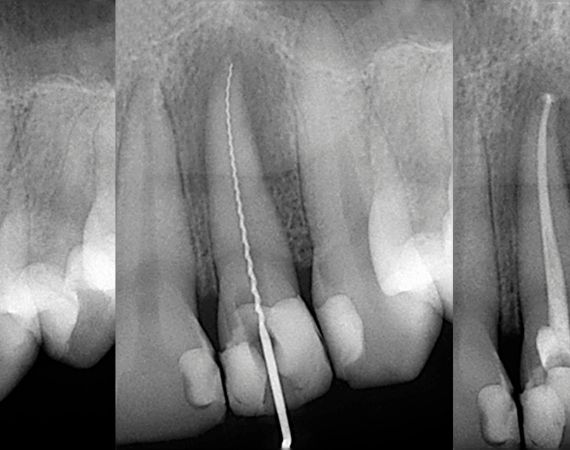

Endodoncia

La endodoncia es un tratamiento que se hace en el interior del diente, más conocido como tratamiento de conductos o tratamiento de nervio, que consiste en retirar el tejido pulpar de los conductos radiculares y rellenarlos con un material inerte biocompatible.

Este tratamiento es necesario cuando, por alguna razón, el nervio sufre un daño irreversible que provoca su infección y, en ocasiones, su muerte (necrosis). La principal causa es la caries no tratada, pero también puede ser por un traumatismo (golpe), una fractura complicada o un desgaste severo.

Los dientes que son sometidos a un tratamiento de endodoncia quedan más frágiles y susceptibles a la fractura debido a la pérdida de vitalidad y, por ende, de humedad e irrigación.